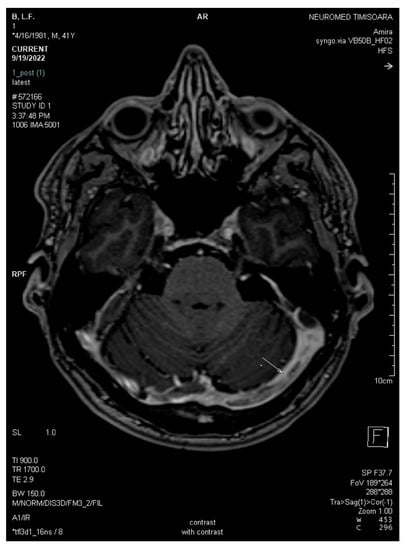

2.2. Neuroimaging Data